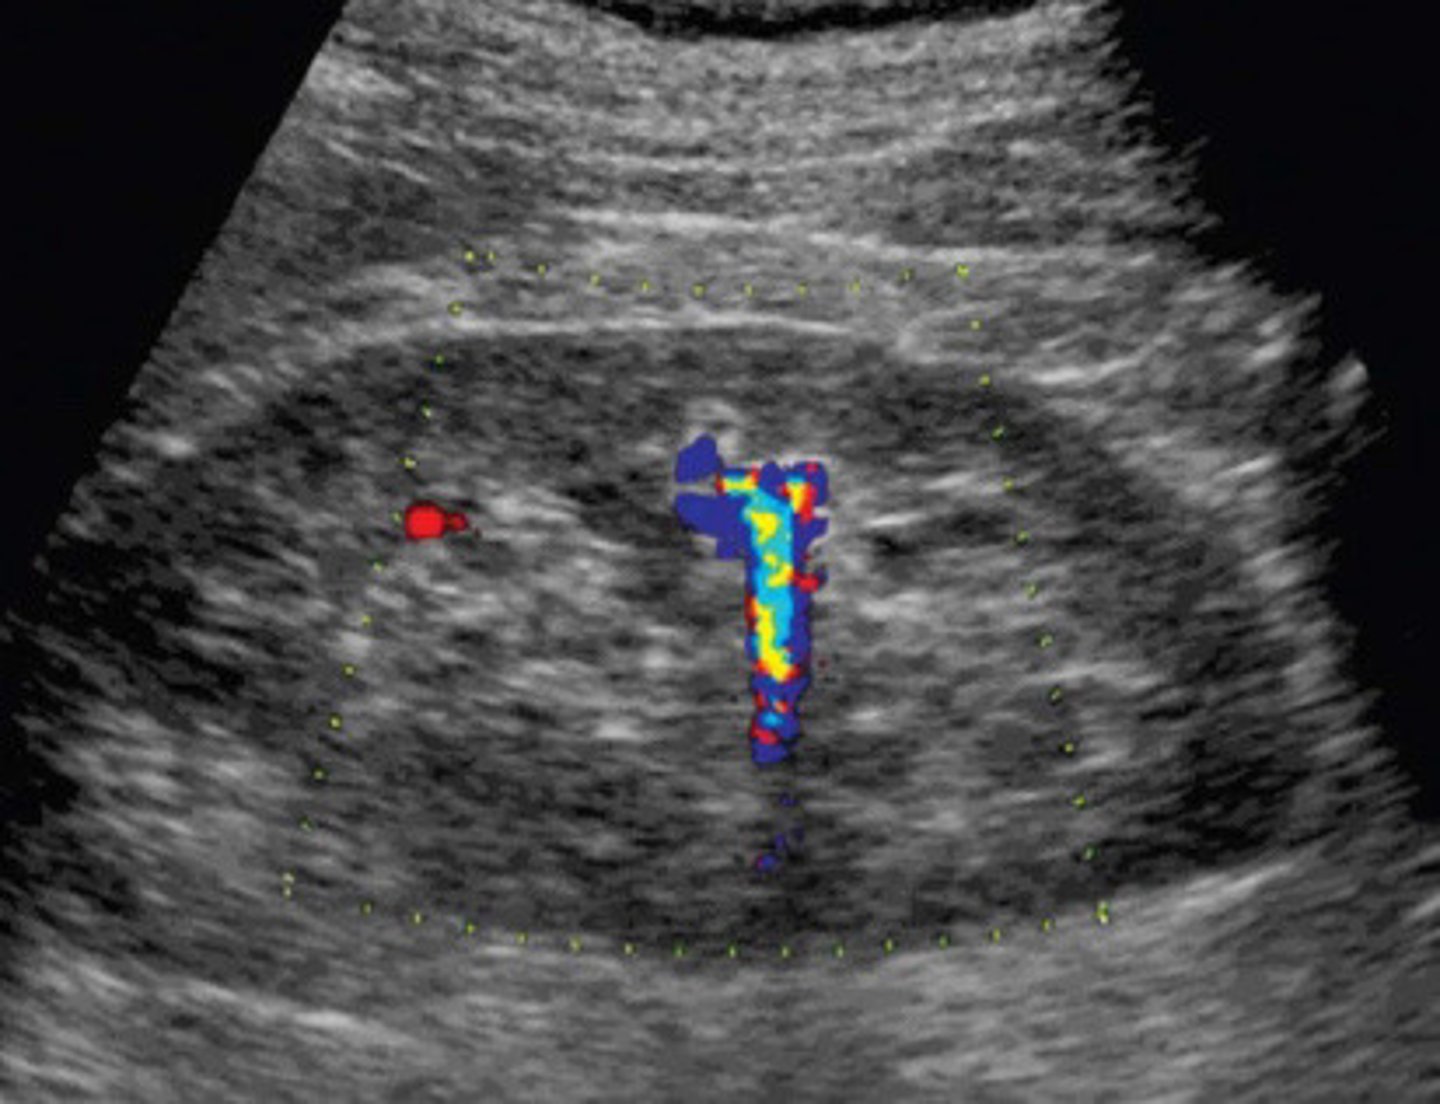

Urethral jet

What does this image show